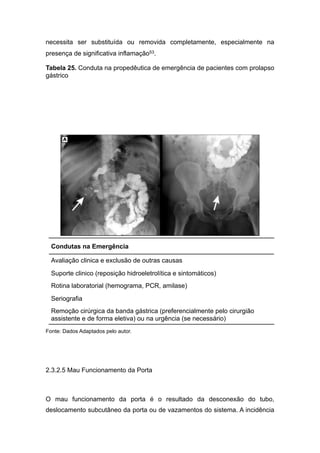

Figura 10. Desenho esquemático prolapso gástrico.........................................41

As complicações tardias incluem erosão da banda gástrica, deslocamento da

banda ou prolapso, mau funcionamento do tubo ou da porta, vazamentos do

sistema, dilatação da bolsa gástrica ou esôfago, e esofagite.

Contudo o maior problema relacionado com banda gástrica é a alta taxa de

reabordagem, tanto por complicações ou resultados insatisfatórios, alcançando

cerca de 50% segundo algumas séries de casos, tanto visando a remoção da

banda gástrica ou mesmo a conversão outra técnica, como o bypass gástrico48.

2.3.2.1 Obstrução do Estoma

Obstrução aguda do estoma é uma complicação precoce mais frequente,